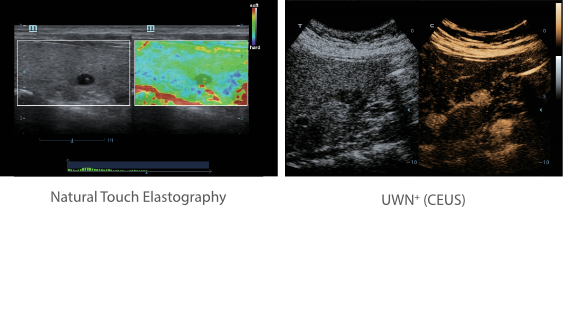

Klinische Bilder